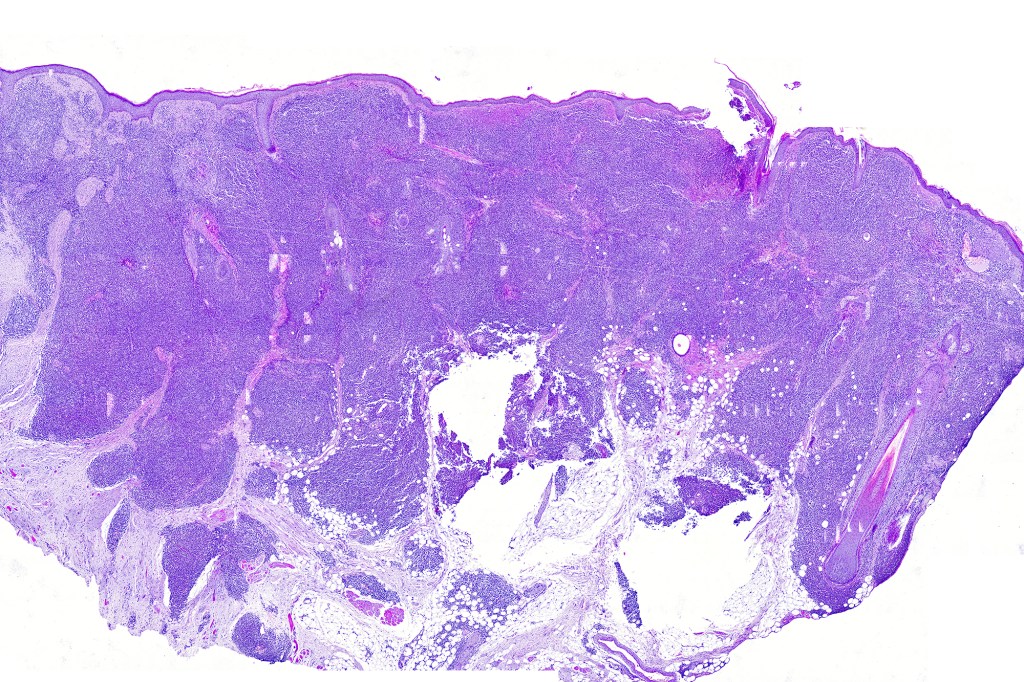

Histological features

. No epidermal involvement

. Dermal +/- subcutaneous fat infiltrate

. No angioinvasion or angiodestruction